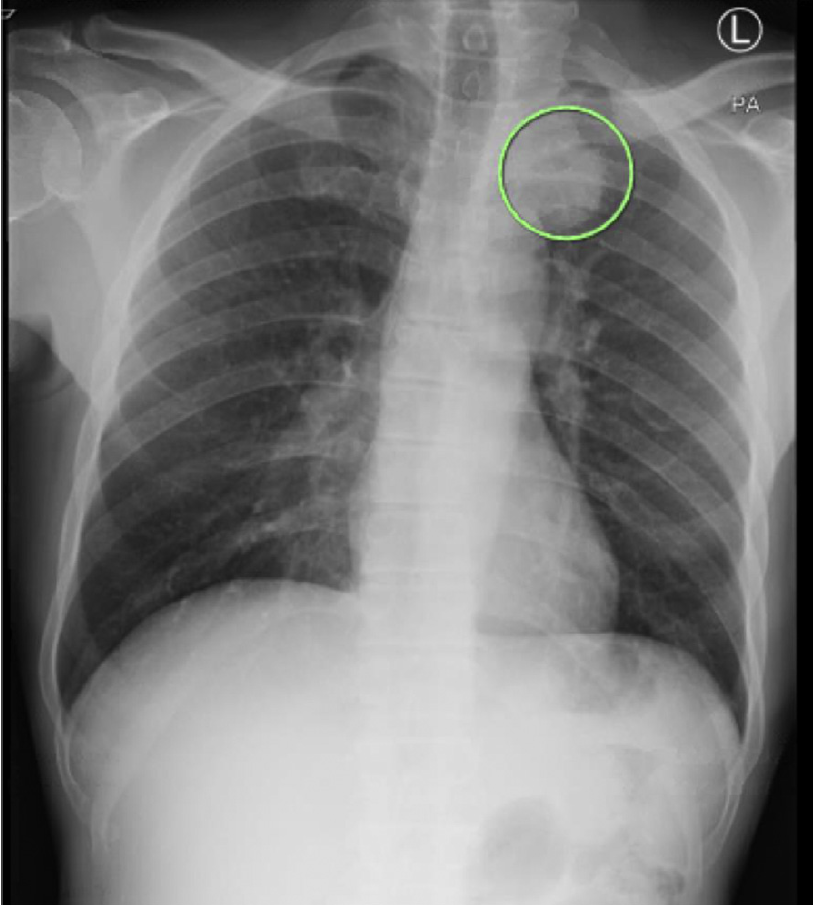

・肺癌検索目的に胸部レントゲン撮影を実施

・胸部レントゲンでは左肺尖部に腫瘤を認めた

・患者は後日気管支鏡検査と生検を受け、非小細胞肺癌の診断となった